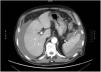

Presentamos el caso de un paciente de 77 años, con antecedentes de enfermedad pulmonar obstructiva crónica GOLD III, adenocarcinoma de pulmón tratado sin evidencia actual de recidiva, flutter auricular anticoagulado con edoxabán, prostatectomía por adenocarcinoma, colecistectomía y hernioplastia inguinal derecha. Acudió por diarrea, astenia y pérdida de peso de varios meses de evolución. Al ingreso se suspendió la anticoagulación oral y se sustituyó por enoxaparina (60mg/12h). Se realizó colonoscopia diagnóstica bajo sedación profunda con propofol, sin dificultad técnica ni complicaciones inmediatas, con diverticulosis como único hallazgo; no se aplicó presión sobre el cuadrante superior izquierdo del abdomen. A las 12 h de la prueba, el paciente comenzó con hipotensión, taquicardia y dolor abdominal generalizado mal controlado con opioides, que describió como progresivo, y de varias horas de evolución. Se extrajo analítica urgente, en la que destacaba anemia de 8.4g/dl (previa 12.9g/dl) y se realizó radiografía de abdomen con la que se descartó perforación. Se completó el estudio con TC abdominal urgente (fig. 1), que mostraba rotura esplénica con extravasación de contraste activo, gran hematoma periesplénico y hemoperitoneo moderado, correspondiente a una lesión esplénica grado V según la American Association for the Surgery of Trauma (AAST). A pesar de la fluidoterapia intensiva, persistía la situación de inestabilidad hemodinámica, por lo que se realizó esplenectomía de urgencia.